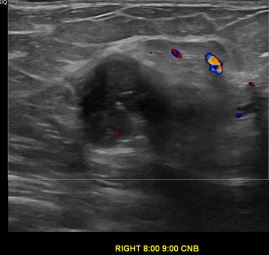

상기환자는 만져지는 멍울있어 검사위해  내원하신 50대 초반

여성분으로 의심스러운 우측유방혹 조직검사 시행해 유방암으로 진단되었습니다